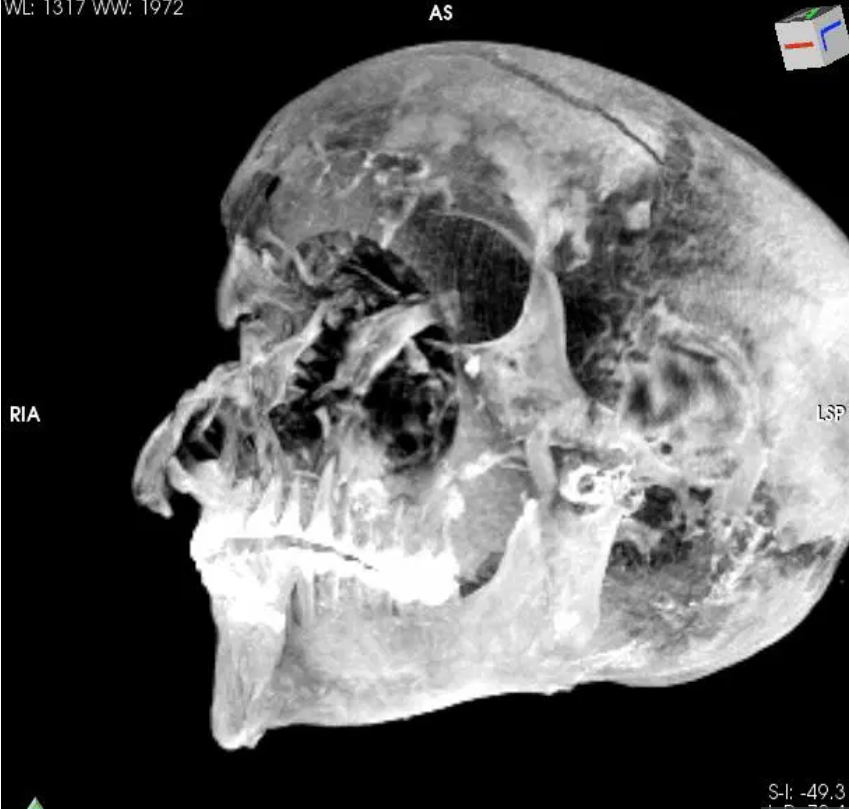

据2021年2月18日《太阳日报(The Sun)》消息 , 一份对木乃伊统治者(the mummy of ruler Seqenenre Tao )发现了木乃伊面部有一个隐藏的较深的伤口 , 猜测这可能正是尸体处理者试图掩盖的伤口 。

通过观察 , 木乃伊似乎受到了各个角度的攻击 , 包括深达骨骼的刺伤 , 面部的割伤 , 眼周和额头的切伤 。

一项最新的非侵入性的医学分析也对陶二世战死的验证做出了贡献 。

研究者们认为 , 陶二世可能双手可能有被捆绑的可能 , 因为他的手臂上并没有任何缠斗造成的伤口 。